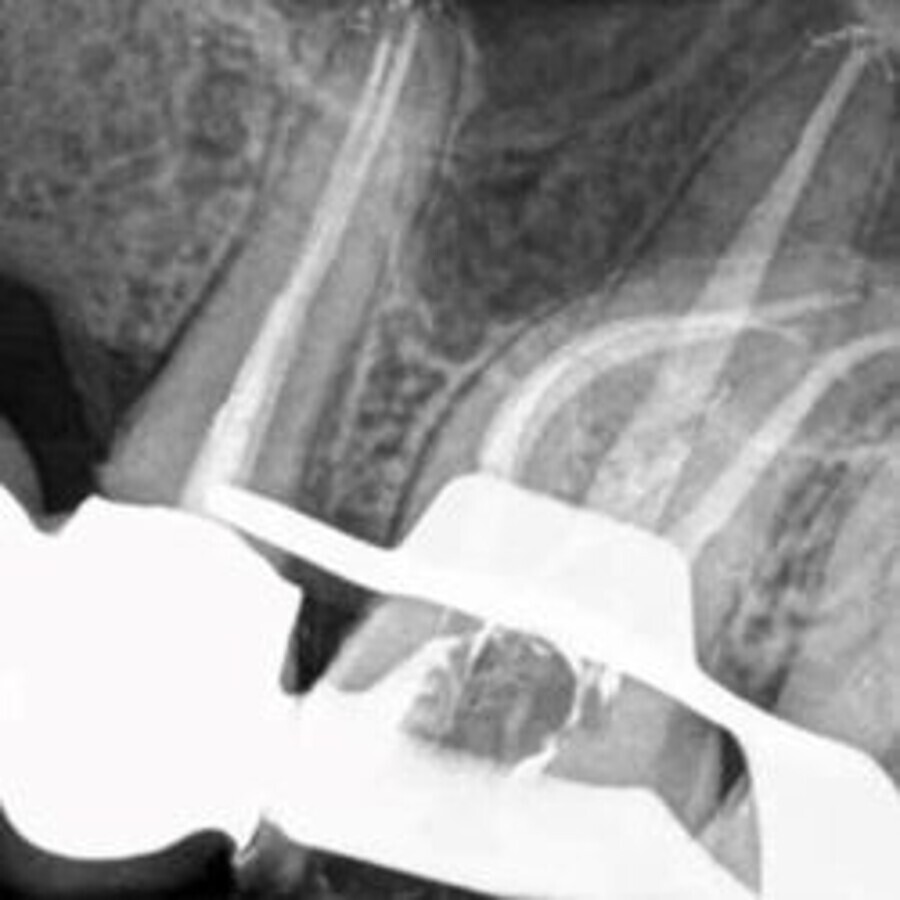

图3:术后X线片。

在清理、成形过程中使用5%次氯酸钠进行大量冲洗。使用超声工作尖(Endo Chuck,EMS)和声波根管冲洗头(EDDY,VDW)进行根管荡洗。最后用17%EDTA冲洗根管(在根管内保留2min)。用吸潮纸尖干燥根管。将环氧胺根管封闭剂和主牙胶尖置于根管内,采用连续波充填技术充填根管。使用玻璃离子水门汀作为暂时填充材料(图3)。将患者转诊至其全科牙科医生进行后续治疗。